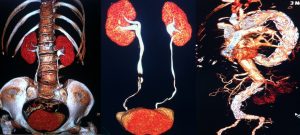

Le ricostruzioni 3D, VR e MIP sono particolarmente utili non solo nel rappresentare lo scheletro e quindi le fratture complesse ma anche nello studio accurato delle strutture vascolari e degli organi profondi. Un particolare software permette di ottenere delle dettagliate immagini di tipo endoscopiche trova impiego nella colonscopia virtuale e anche nella broncoscopia virtuale, esami particolarmente utili soprattutto quando l’esame endoscopico non puo essere eseguito o quando viene interrotto. Altra fondamentale applicazione è la TC ad alta risoluzione del polmone, un esame che viene acquisito o successivamente ricostruito con precisi parametri dedicati per lo studio delle più fini strutture polmonari utile nello studio delle patologie interstiziali polmonare (HRTC).

- Urologica: meglio nota come uroTC, è una delle particolari varianti della TC con contrasto che permette di analizzare nei dettagli l’anatomia e la funzione di reni, ureterie vescica (apparato urinario).

- Angio TC: particolare variante della TC con contrasto che focalizza le attenzioni sulla circolazione sanguigna all’interno dei vasi sanguigni arteriosie venosi del corpo.